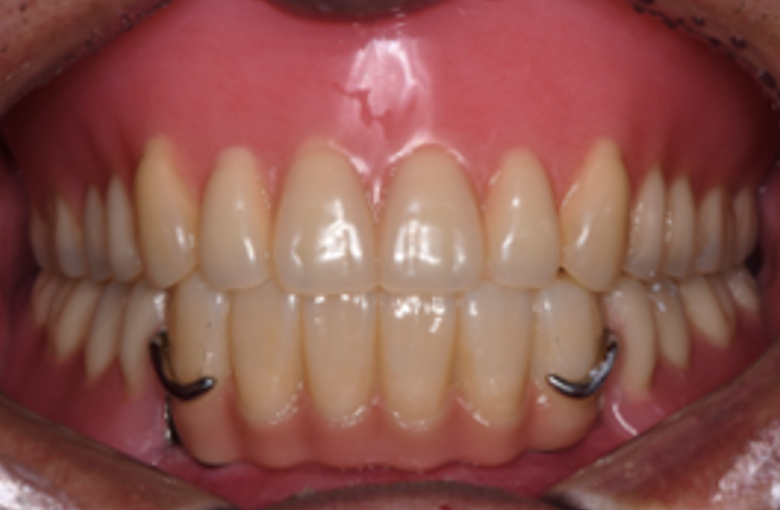

하악 부분 틀니 및 상악 전체 틀니 제작 후

따라서 아래쪽 앞니 쪽에 틀니를 잡아줄 수 있는 임플란트 두 개를 식립하여 두 개의 임플란트들을 연결하여 아래 앞니 6개를 만들어 드린 후, 어금니쪽은 부분 틀니로 보강하는 치료 방법을 선택하였습니다. 위쪽은 전체 틀니를 만들어 드렸습니다.

임플란트를 이용하여 부분적으로 치아를 만들고, 이 치아에 일정 부분의 힘을 지탱시키는 형식의 부분틀니는 전체 틀니에 비해 씹는 힘에 잘 버티고 혀나 볼의 움직임에 틀니가 탈락하지 않아 치료가 잘 마무리 되었습니다.